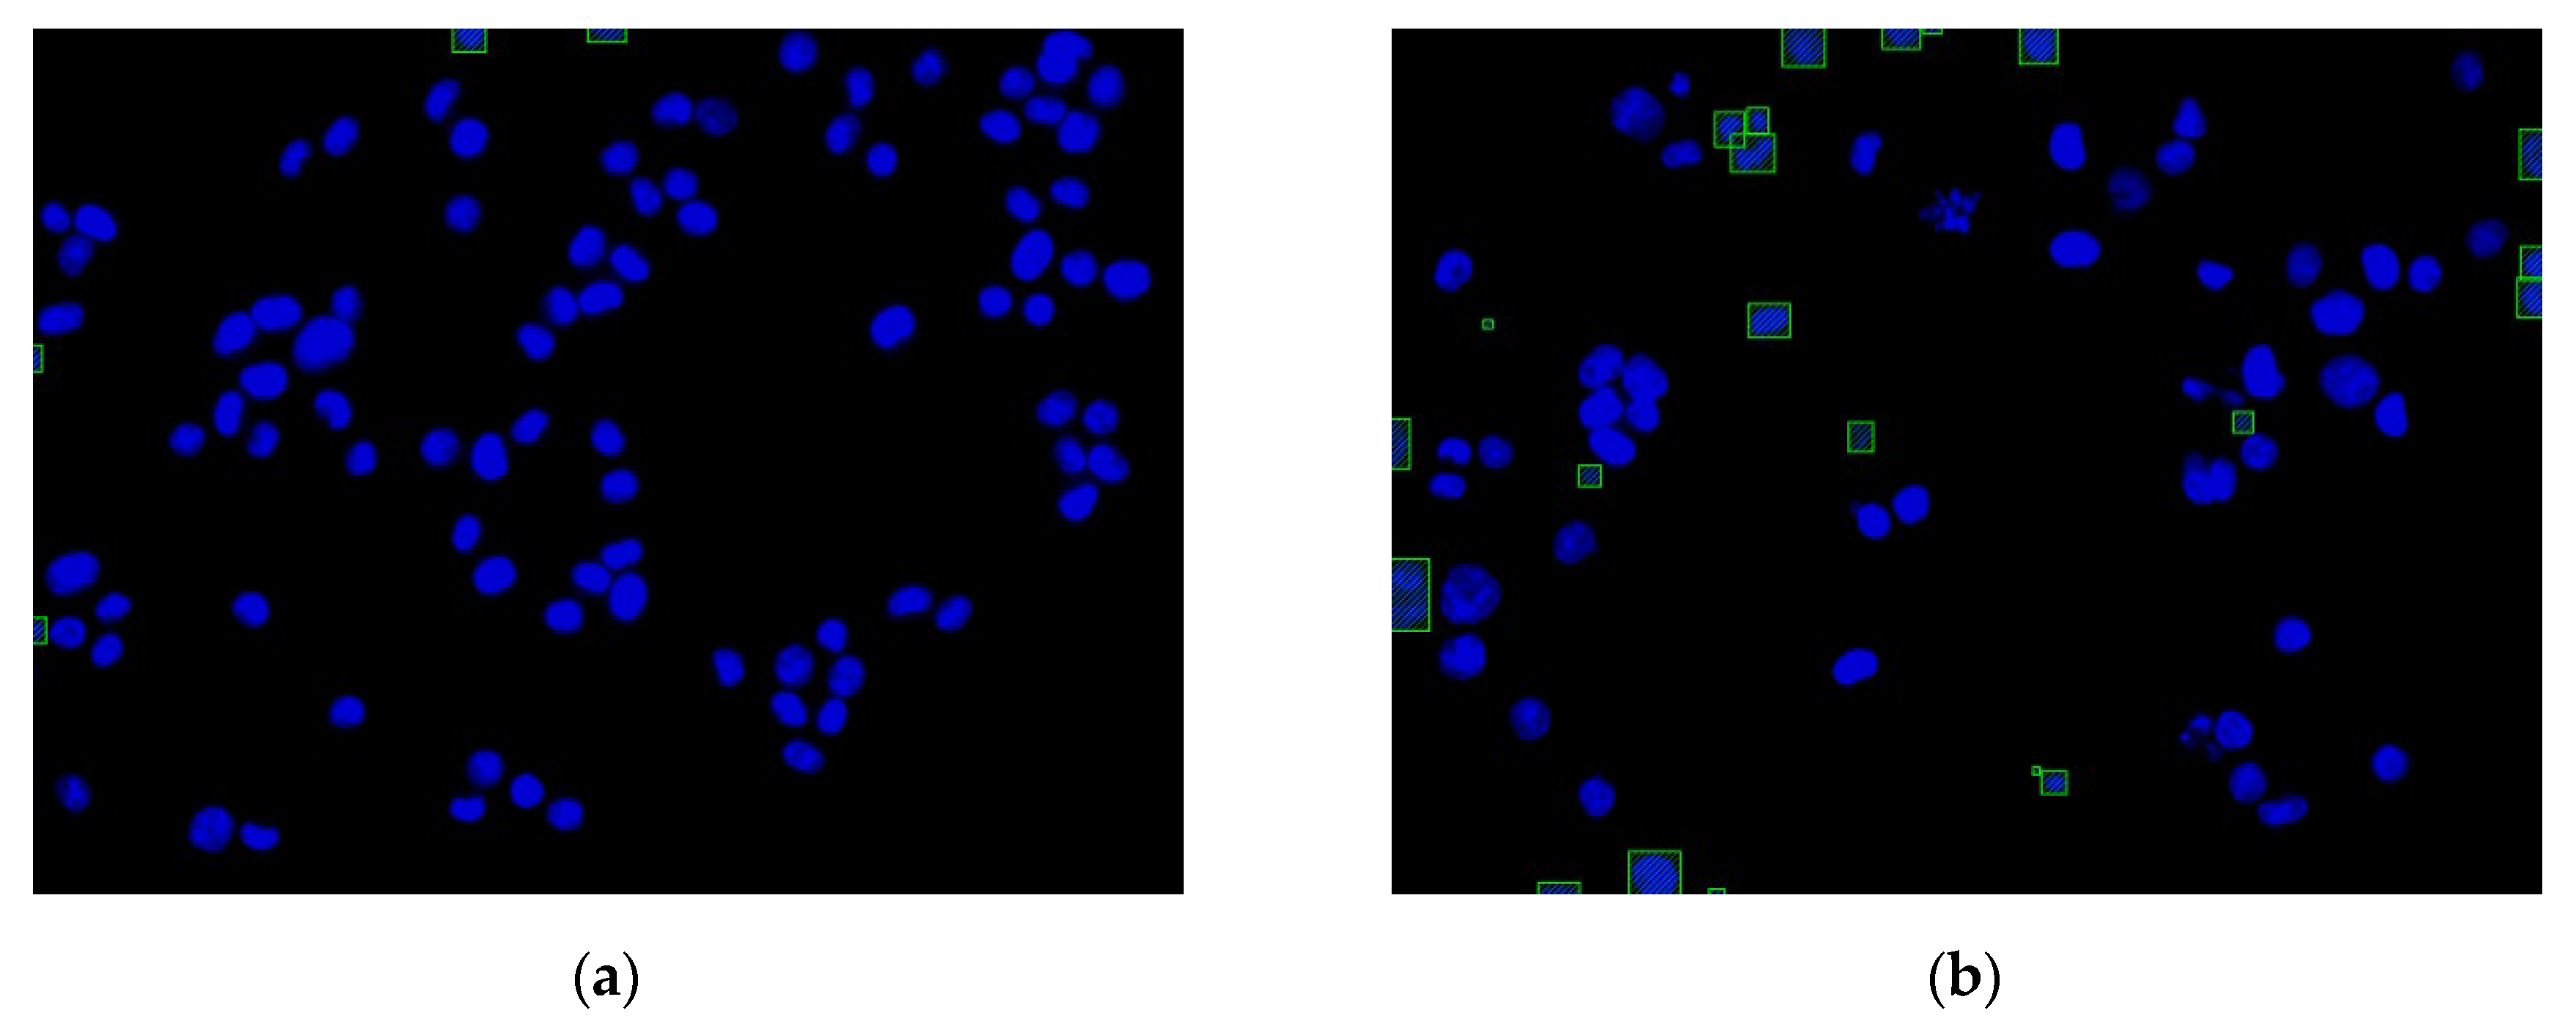

Figure 13 shows the function of each step in this experiment. The images of the cell nuclei and cytoskeleton are shown in Figure 13, which is separated from Figure 9. We used k-means clustering [38] for the color quantization of blue elements in the images (the number of quantized colors, k = 15). The background was then removed to obtain the cell nucleus regions, and the lowest quantized color grayscale value was used as the background color. The regions with values higher than the background color are considered to be the cell nucleus and cytoskeleton regions. Figure 13 shows the results: Figure 13a1–a4 show the images after color quantization, while Figure 13b1–b4 show the cell nucleus and cytoskeleton regions after the background is removed. We used the cytoskeleton region (N) to obtain the valid cell nucleus regions (N∩C), and the results are shown in Figure 14. After the P (=N−B−D) operation, no valid regions were present in Figure 14a (the four regions are located at the edges of the image). However, Figure 14b contains 10 invalid regions, and 12 regions are located at the edges of the image (rectangular box with diagonal lines).

Figure 13.

Image color quantization and background removal: (a1,a3) color quantization of the nucleus images; (a2,a4) color quantization of the cytoskeleton images; (b1,b3) nucleus regions (N); (b2,b4) cytoskeleton regions (C).